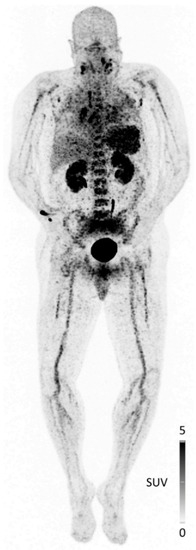

- Herrmann, K.; Lapa, C.; Wester, H.J.; Schottelius, M.; Schiepers, C.; Eberlein, U.; Bluemel, C.; Keller, U.; Knop, S.; Kropf, S.; et al. Biodistribution and radiation dosimetry for the chemokine receptor CXCR4-targeting probe 68Ga-pentixafor. J. Nucl. Med. 2015, 56, 410–416. [Google Scholar] [CrossRef] [PubMed] [Green Version]